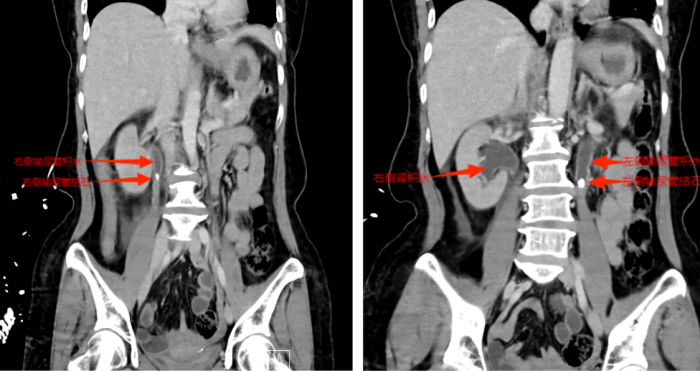

等到第二天送医时,张小华血压已降至78/42mmHg(血压<90/60mmHg称为休克血压),CT结果显示其双侧输尿管结石引发尿路梗阻,导致尿源性脓毒血症合并脓毒性休克。立博体育 立即启动MDT多学科诊疗,泌尿外科一区主任傅发军带领团队紧急在急诊ICU实施床旁输尿管支架置入术,迅速解除梗阻,经抗感染等综合治疗,患者最终转危为安。目前,张小华已康复出院,择期再返院处理双侧输尿管结石。

CT显示双侧输尿管结石、肾积水